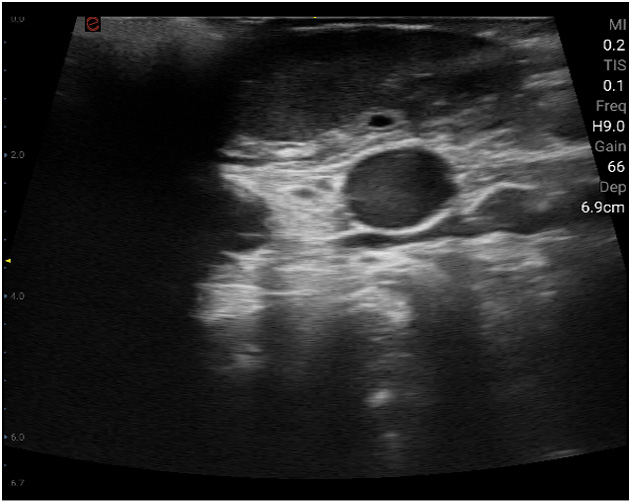

Esaote Q7 Vet er et trådløst, håndholdt ultralydapparat dedikert for veterinærer. Spesialtilpassete forhåndsinnstillinger og software og database designet for dyr. Esaote Q7 kombinerer kraften til moderne ultralydteknologi med brukervennlighet og mobilitet.

Med håndholdt ultralyd og en smartmobil/nettbrett, kan du gjøre raske og gode undersøkelser med Esaote Q7. Dets trådløse design gjør det mulig å utføre ultralydundersøkelser av høy kvalitet når som helst og hvor som helst. Alt er tilrettelagt for en vellykket undersøkelse.